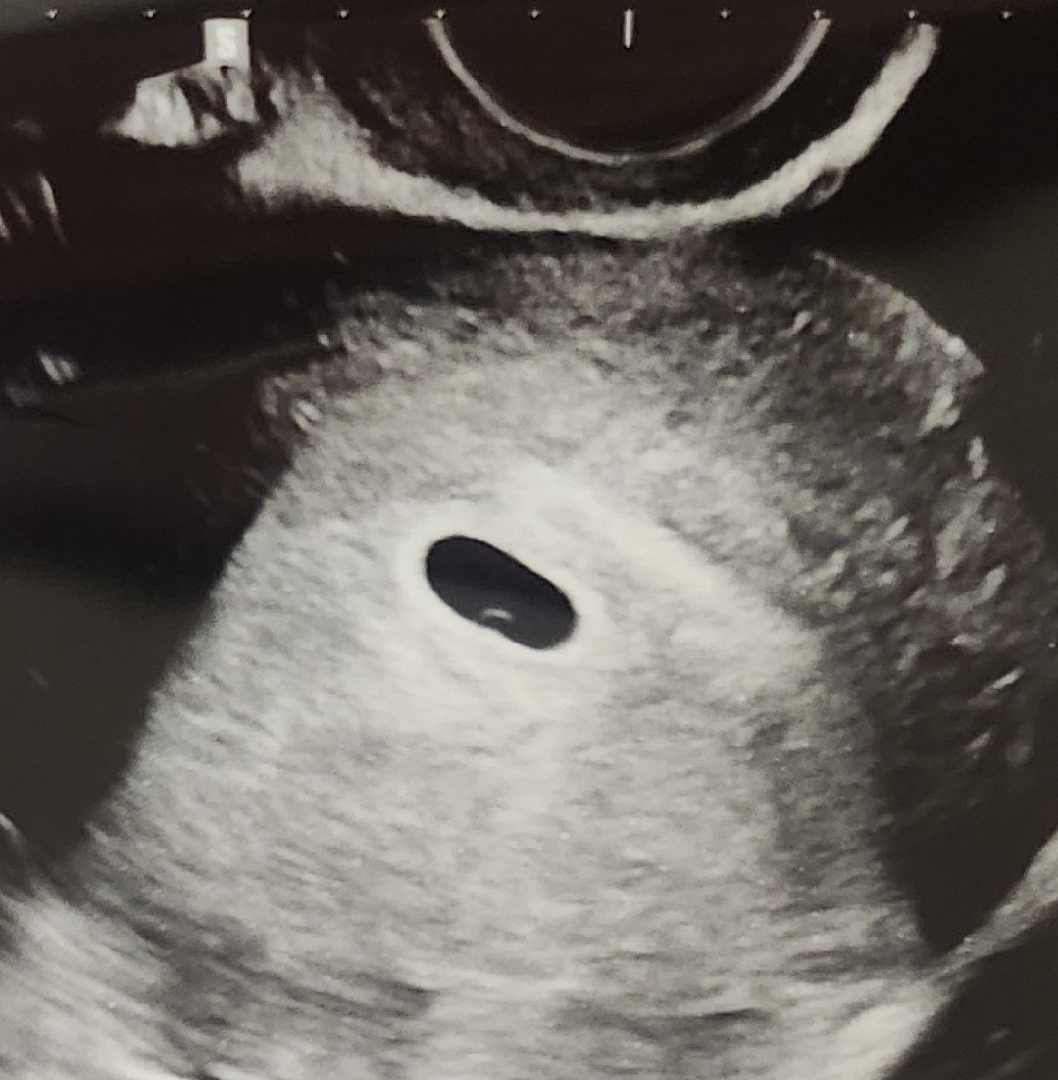

6월 15일 마지막생리고 주기는 28일로 비교적 규칙적이었는데 오늘 초음파 보니 5mm 정도 아가집이 뿅 나타났네요☺️ 2주 기다리면 아가 볼 수 있다고 하시는데 과연 기다릴 수 있을까요? 원장님도 직원분들도 다 축하한다 해주셔서 기쁘네요 앞으로도 별일 없이 쑥쑥 잘 자라주길🩷